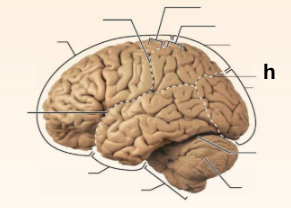

Identify the structure labeled “a” in the image.

Brain Stem

Identify the structure labeled “b” in the image.

Central culcus

Identify the structure labeled “c” in the image.

Cerebellum

Identify the structure labeled “d” in the image.

Frontal lobe

Identify the structure labeled “e” in the image.

Lateral sulcus

Identify the structure labeled “f” in the image.

Occipital lobe

Identify the structure labeled “g” in the image.

Parietal lobe

Identify the structure labeled “h” in the image.

Parieto-occipital sulcus

Identify the structure labeled “i” in the image.

Postcentral gyrus

Identify the structure labeled “j” in the image.

Precentral gyrus

Identify the structure labeled “k” in the image.

Temporal lobe

Identify the structure labeled “l” in the image.

Transverse cerebral fissure